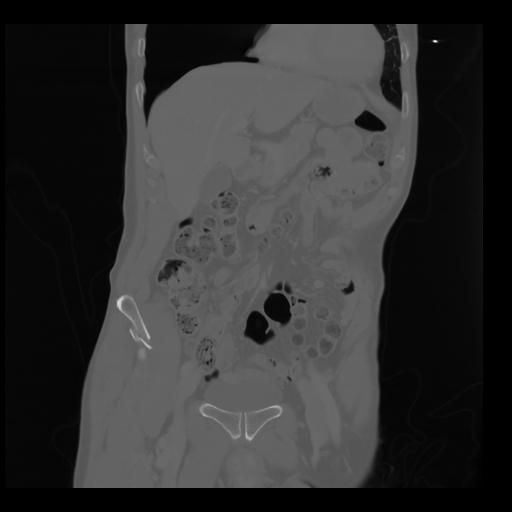

35 CUERPO,CE,Coronal,3.000,CUERPO,Coronal,